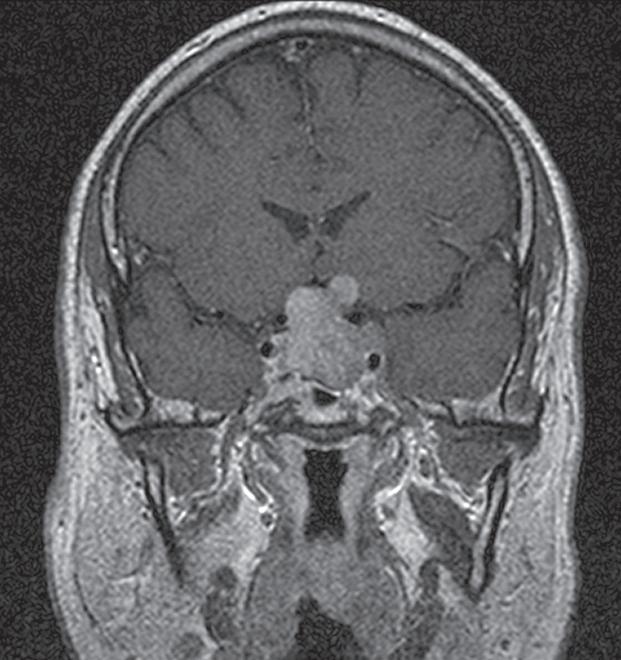

Obr. 1. Makroadenom hypofýzy s výraznou suprasellární extenzí a tlakem na chiasma opticum.

Fig. 1. Pituitary macroadenoma with marked suprasellar extension and pressure on the chiasma opticum.

U 3 z nich byl na magnetické rezonanci popsán makroadenom hypofýzy (obr.  1), u 4 mikroadenom a u 4 mužů magnetická rezonance žádný patologický nález neprokázala. Všem mužům bylo provedeno endokrinologické vyšetření.

U 3 mužů byla hyperprolaktiném ie způsobena p ou ze polékově – tito muži užívali ně kte rý typ psychofarmak se schopností blokace dopaminergního tuber oi nfundibulárního systému hypotalamu. Celkem 8 mužům byla nasazena terapie cabergolinem (Dostinex ®) v dávce 0,25–0,5 mg 1– 2× týdně. Celkem 3 muži s prokázaným makr oa denomem byli odesláni k n eu rochirurgickému operačnímu řešení. Závažnost ED jsme hodnotili pět io tázkovou form ou dotazníku Internat io nal Index of Erectile Funct io n (IIEF-5) (obr. 2).